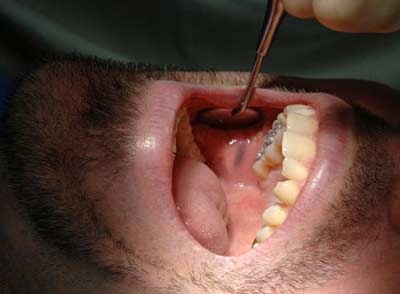

Đừng lờ đi những vết viêm nhiễm trong khoang miệng nếu chúng tồn tại nhiều tuần liên tiếp, vì đó có thể là ung thư